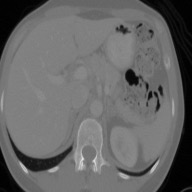

This work presents a novel framework CISFA (Contrastive Image synthesis and Self-supervised Feature Adaptation)that builds on image domain translation and unsupervised feature adaptation for cross-modality biomedical image segmentation. Different from existing works, we use a one-sided generative model and add a weighted patch-wise contrastive loss between sampled patches of the input image and the corresponding synthetic image, which serves as shape constraints. Moreover, we notice that the generated images and input images share similar structural information but are in different modalities. As such, we enforce contrastive losses on the generated images and the input images to train the encoder of a segmentation model to minimize the discrepancy between paired images in the learned embedding space. Compared with existing works that rely on adversarial learning for feature adaptation, such a method enables the encoder to learn domain-independent features in a more explicit way. We extensively evaluate our methods on segmentation tasks containing CT and MRI images for abdominal cavities and whole hearts. Experimental results show that the proposed framework not only outputs synthetic images with less distortion of organ shapes, but also outperforms state-of-the-art domain adaptation methods by a large margin.